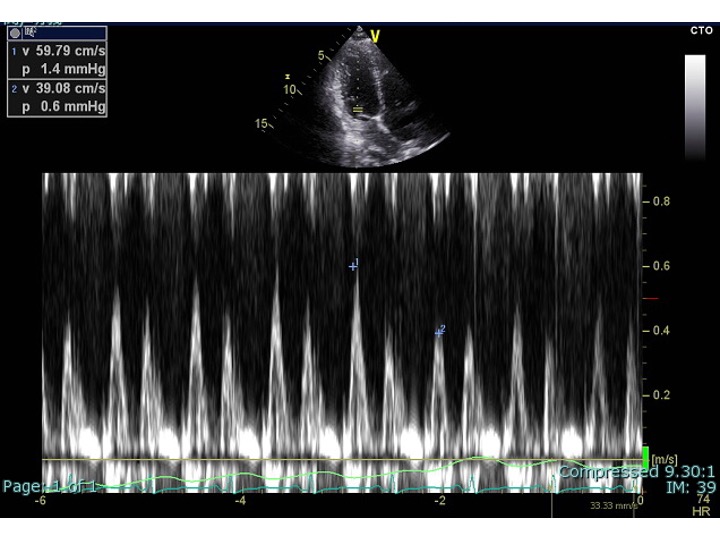

ransthoracic echocardiography was performed: Although the left ventricular ejection fraction was preserved, the inferior vena cava was dilated and showed no respiratory variation. There were pericardial adhesion and a septal bounce (Fig2-4). He was suspected of having constrictive pericarditis and was admitted for further evaluation.